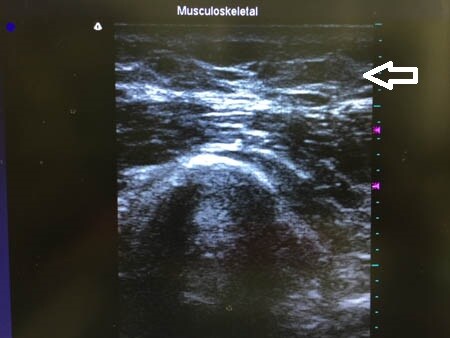

同様に右二の腕。 ↓ ↓ ↓

↓ ↓ ↓

今回紹介した患者様の脂肪吸引は

相変わらずの大盛況のため

特別手術枠の早朝から行われました。